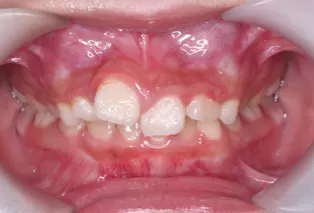

Intraoral photos